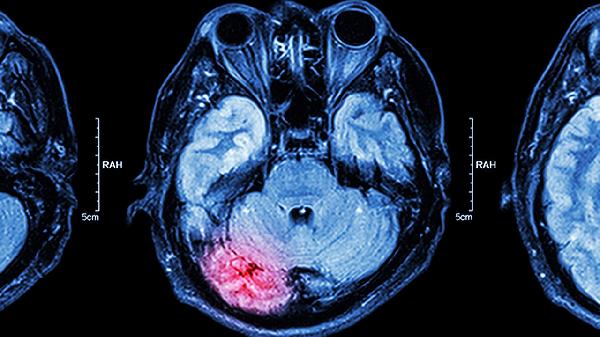

3、感染的症状与处理:如果发生颅内感染,患者可能会出现发热、头痛、呕吐等症状,严重时可能导致脑水肿或脓毒症。这些症状需要引起重视,及时就医。医生会通过影像学检查和实验室检测来确认感染的存在,并采取相应的治疗措施。